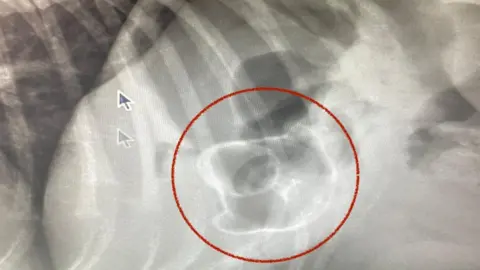

My Family Vets/PA MediaSenior vet Debs Smith said the X-ray on Ronnie's stomach showed the duck "really clearly".

"It was still in his stomach and hadn't passed into the intestines, but we were obviously concerned about it causing an obstruction," she said.